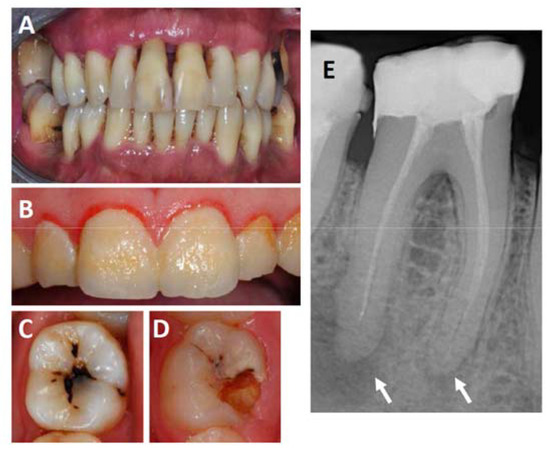

2. Oral Infections: Periodontitis, Gingivitis and Endodontic Lesions